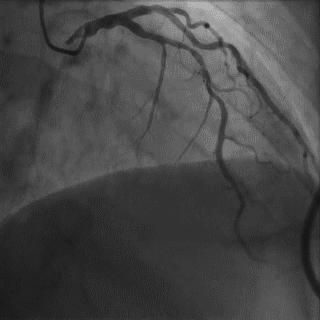

2014年,Patel T等首先采用球囊辅助通过技术(Balloon-assisted tracking,BAT),用于通过桡动脉途径中扭曲、细小节段(包括严重痉挛节段)(图1-2)。

图1

图2 BAT技术应用实例1。52岁女性患者冠脉严重痉挛(A),注射2次鸡尾酒后仍未缓解(B),采用BAT技术(C),顺利介导7F指引导管通过桡动脉严重痉挛节段(D)